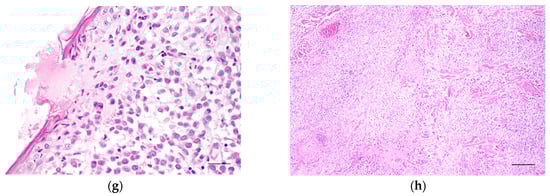

Figure 1.

Light microscopy images of canine cutaneous histiocytoma. (a) Tumour cells occupy the superficial dermis. Scale bar = 60 μm; (b) cells with indistinct contours and vesiculated nuclei with occasional nucleolus. Scale bar = 30 μm; (c) epidermal “invasion” by the neoplastic cells of the canine cutaneous histiocytoma. Scale bar = 60 μm; (d) epidermal “invasion” by neoplastic cells (higher magnification). Scale bar = 30 μm; (e) extensive ulceration of the epidermis. Scale bar = 120 μm; (f) pseudocarcinomatous hyperplasia of the epidermis. Scale bar = 60 μm; (g) small epidermal ulcer in the epidermis covering the CCH. Scale bar = 30 μm; (h) moderate areas of necrosis at the periphery and centre of the tumour. Scale bar = 120 μm.

Canine cutaneous histiocytoma presented as an expansively growing neoplasm composed of mononuclear cells that exhibit moderate pleomorphism and are distributed up to the dermo-epidermal junction (Figure 1a). The cytoplasm of the neoplastic cells varied from scant to abundant and was either acidophilic or occasionally vacuolated. The nuclei were voluminous, generally eccentric, and exhibited hyperchromasia or a vesicular appearance with peripheral hyperchromasia. They were oval, round, or kidney-shaped, with prominently visible nucleoli (Figure 1b).

Mitotic figures were frequently observed, ranging from 0 to 12 per high-power field. Signs of individual cell death were commonly noted throughout the samples. The tumour stroma was typically sparse (77.4% of cases) and exhibited low vascularity, with no apparent increase in blood vessels compared to the normal dermis. Collagenisation was occasionally observed in some areas.

Epidermal “invasion” by tumour cells was frequently observed (Figure 1c,d). The overlying epidermis exhibited varying characteristics: in seven cases (7.5%), it appeared normal; in 32 cases (58%), it was ulcerated across its entire extent (Figure 1e); and in 35 cases (37.6%), it exhibited pseudocarcinomatous hyperplasia with features such as acanthosis, hypergranulosis, and hyperkeratosis (Figure 1f). At the locations of the epidermal papillae, the tumour surfaced through the epidermis with a blurred demarcation between the two zones. In eight lesions (8.6%), superficial fibrosis areas were observed, separating the epidermis from the tumour.

Ulceration was present in 83 (89%) of the preparations; however, in 20 cases (21.2%), the ulcers were small and only visible under a microscope (Figure 1g). Typically, a superficial neutrophil infiltrate was associated with the ulceration. Around the ulcerated regions, a reduction in the number of epidermal layers was observed, along with a thinning of the germinative and spinous strata. The basal membrane was absent in these areas, indicating epidermal invasion by tumour cells.

In over half of the cases (63.3%), necrosis was moderate and located at the basolateral periphery and the centre of the tumour. These areas were characterised by a hypocellular central region with acidophilic amorphous debris and occasionally pyknotic nuclear remnants (Figure 1h). Necrosis was absent in 33 cases (35.5%).